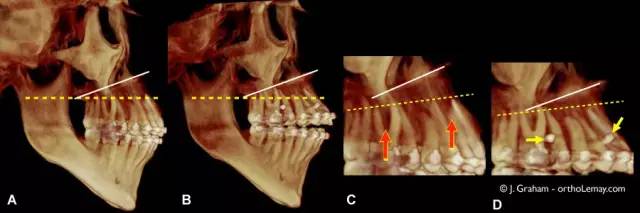

锥束CT(CBCT)图像

锥束CT图像(CBCT)呈现出微种植钉的位置。

(A)右视图、前视图及左视图。(B)咬合面视图,能看出微种植钉嵌在牙根之间。

锥束CT(CBCT)。最初及最终治疗阶段。

3D扫描下,牙列抬高前后牙齿垂直方向位置的变化(CBCT)。